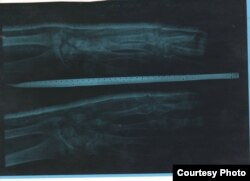

Муҳатдин Юсуповнинг айтишича, бу унинг синдирилган қўли рентген тасвири